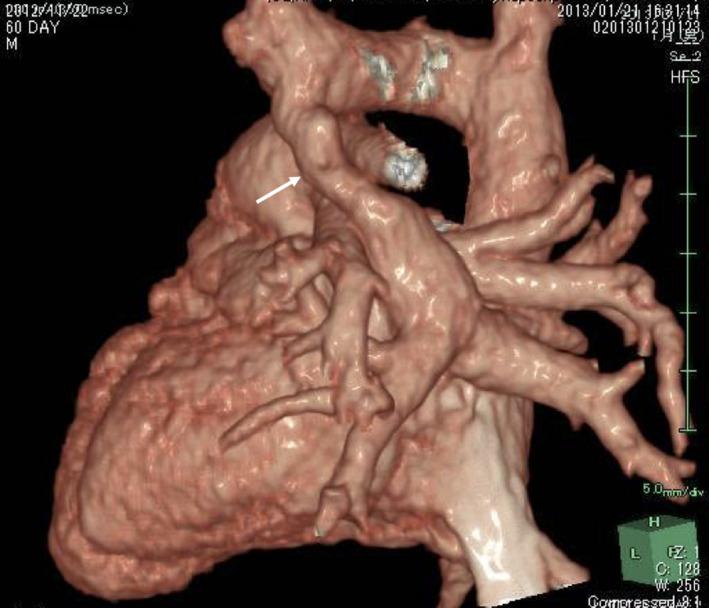

Double drainage of total anomalous pulmonary venous connection revealed after surgical repair of a supracardiac total anomalous pulmonary venous connection.

Mixed type TAPVC with double drainage, where the second vertical vein enlarged rather than atrophied after surgery. If we did not recognize left-to-right shunting before surgery, it can be treated with catheterization as demonstrated by our case.